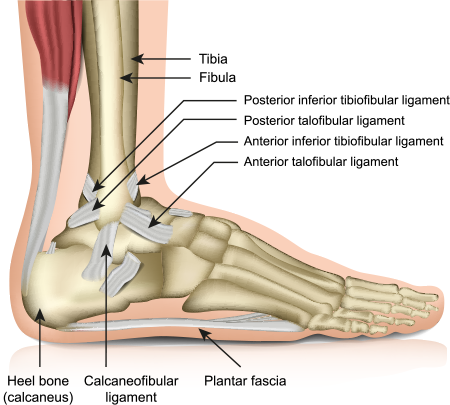

Heel Pain Causes and Treatment shop, Heel Pain Causes Diagnosis Treatment shop, 4 Heel Pain Symptoms to Take Seriously Chicagoland Foot and Ankle Board Certified Foot and Ankle Specialists and Surgeons shop, Ankle Heel Foot Pain SpinePain Solutions shop, 10 Causes of Heel Pain and When to See a Doctor Raleigh Orthopaedic shop, Heel Pain Plantar Fasciitis is a common and Painful Condition shop, Understanding Foot Pain Foot Pain Chart Foot Pain Diagram Pain Medicine Consultants Pain Specialists shop, Pain In The Back Of The Heel What Could It Mean shop, Pain In The Back Of The Heel What Could It Mean shop, Main Causes of Back of Heel Pain in North Seattle Foot and Ankle Center of Lake City shop, What Causes Heel Pain shop, Not all heel pain is Plantar Fasciitis RunningPhysio shop, Common Conditions Causing Heel Pain shop, Common Causes of Pain in the Back of the Ankles Pain Management NYC shop, Plantar Fasciitis Foot and Ankle Specialists shop, Diagnosis of Heel Pain AAFP shop, Heel pain s latest treatment techniques A Step Ahead Foot and Ankle Care shop, Ankle Heel Pain Treatment Specialists DPMC shop, Heel Pain Causes Treatment Prevention Podiatry Sydney shop, Medial Ankle Pain Tarsal Tunnel Syndrome Sports Injury Physio shop, A Stabbing Heel Pain shop, Foot Pain Conditions Causes Symptoms Treatments HSS shop, Pinpoint Your Foot Ankle Pain OrthoNebraska shop, What is heel pain Sole Podiatry shop, Foot and Ankle Pain Treatment in New Jersey RWJBarnabas Health shop, Heel Pain Causes Diagnosis and Treatment Options Joint Replacement Institute shop, Severs Disease Sever s Disease Treatment Sydney shop, Plantar Fasciitis Symptoms Causes Treatment Options shop, Ankle Pain and Plantar Fasciitis Treatment Softwave Clinics shop, Side Heel Pain What You Should Know Cellaxys shop, Foot Pain Conditions Causes Symptoms Treatments HSS shop, Effective Treatment for Heel Pain Foot Foundation shop, Heel Pain Podiatrist in Old Bridge and Sayreville NJ Jason Grossman DPM shop, Foot and Ankle Pain Treatment in Schertz BioMotion PT shop, Achilles Tendinopathy Causes Symptoms Treatment The Feet People Podiatry shop.